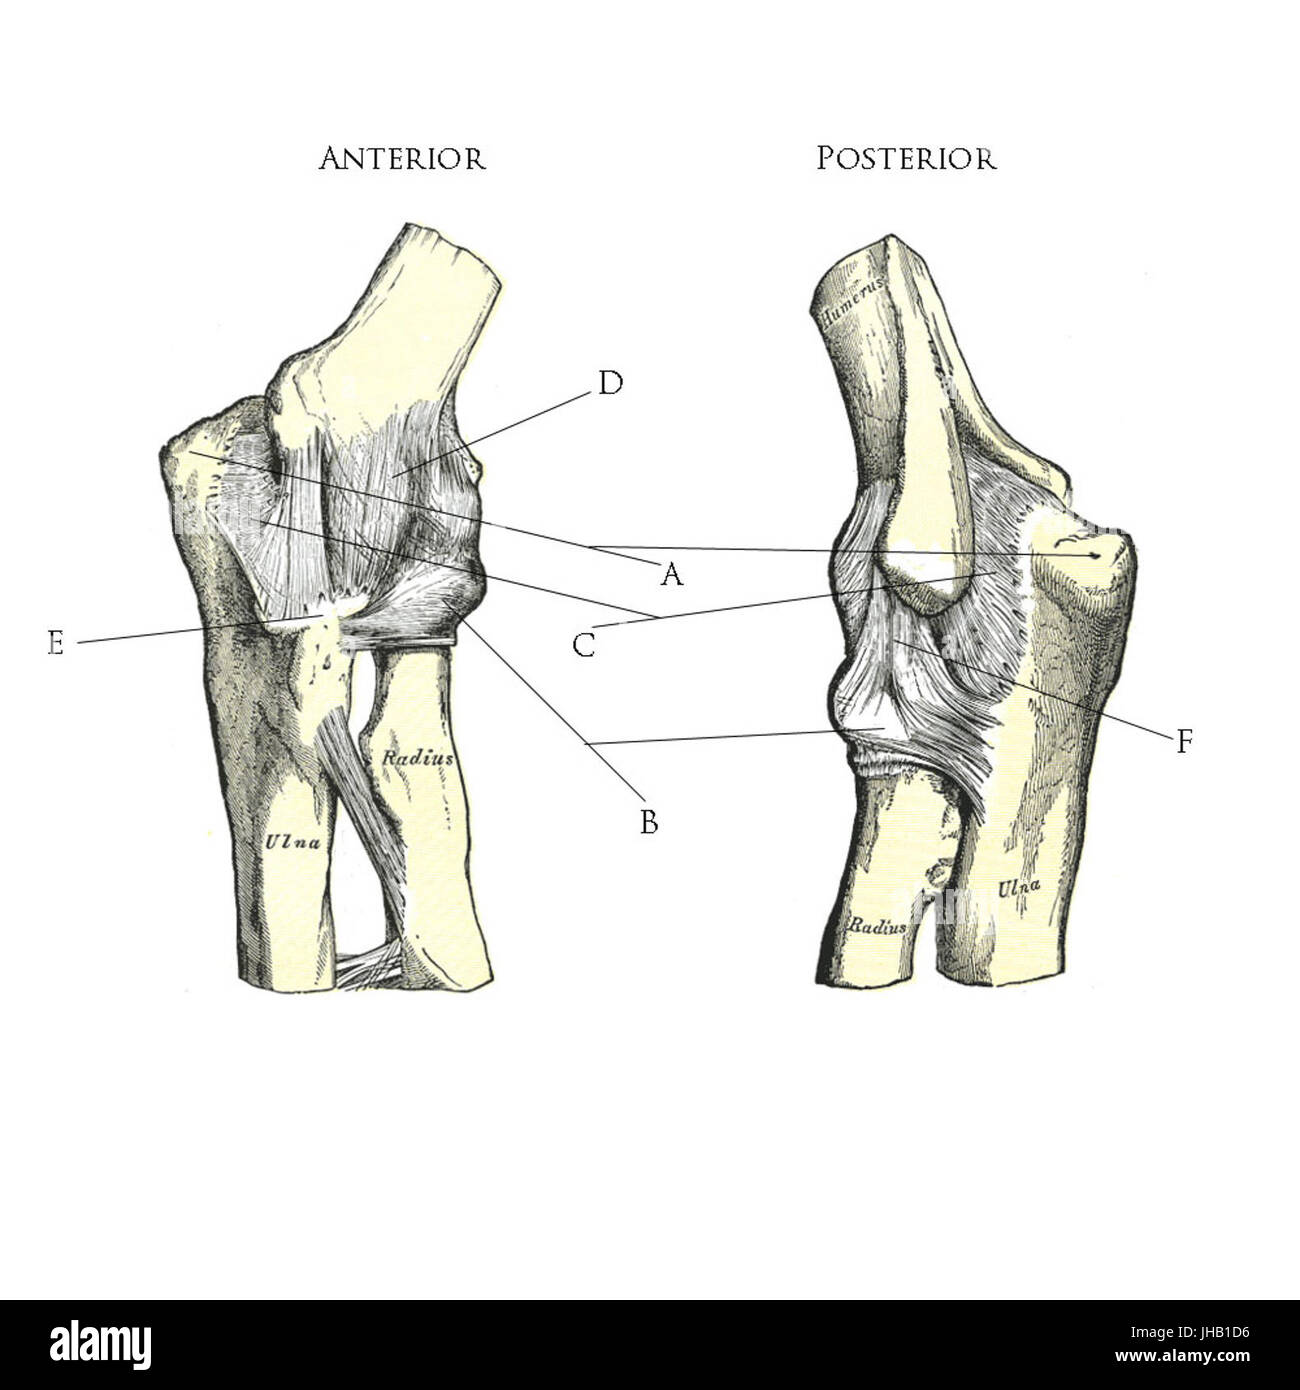

RF2BTGJYJ–Der Humerus ist ein langer Knochen des oberen Gliedes zwischen Ellenbogengelenk und Schulter, Vintage-Linie Zeichnung oder Gravur Illustration.

RF2JNYJM7–Präzise Knochen des Arms oder der oberen Extremität des menschlichen Skelettsystems oder Skeletts isoliert auf weißem Hintergrund 3D Rendering Illustration. Anterior und